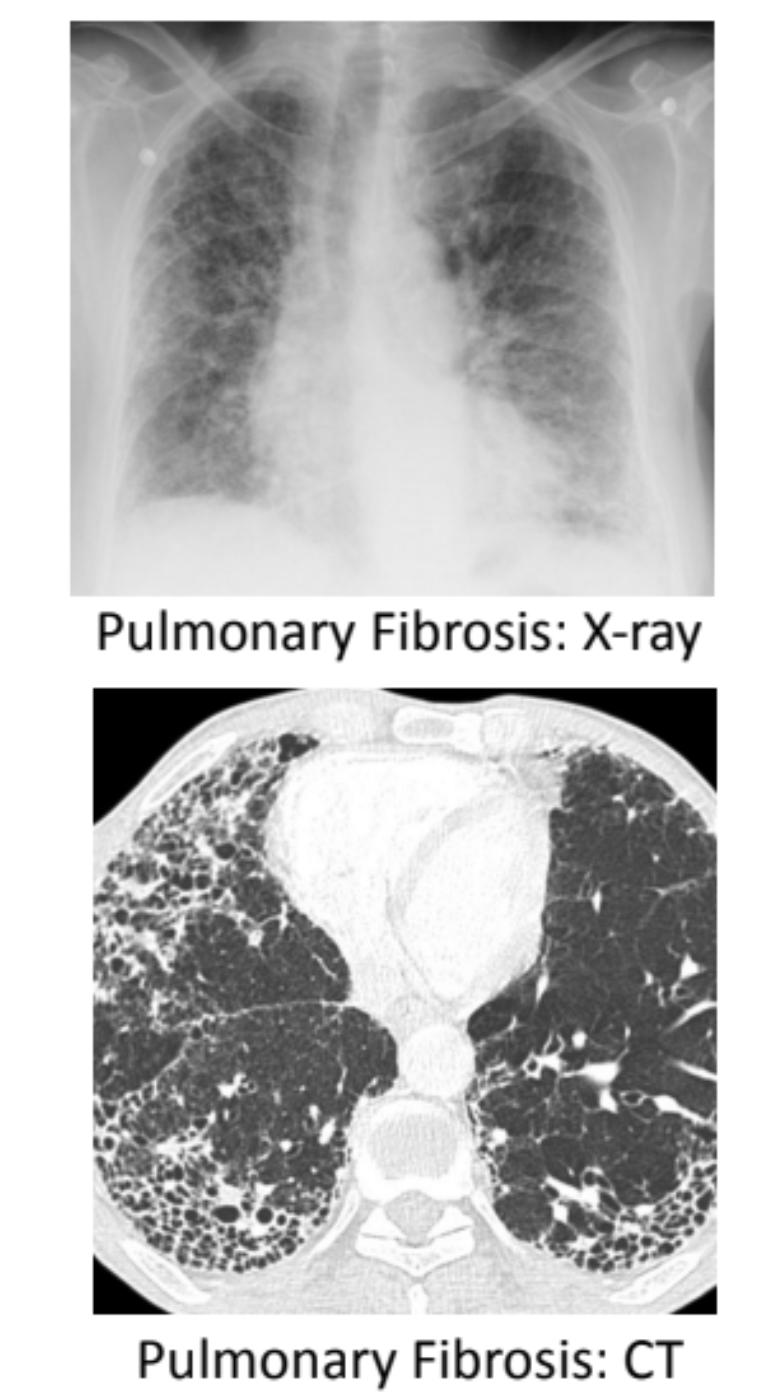

_ imaging is often used for the diagnosis of IPF in which _ and _ will be observed

CXR/CT imaging is often used for the diagnosis of IPF in which bilateral diffuse reticulonodular opacities and honeycombing will be observed

* Looks like a net-like pattern of nodular fibrosis